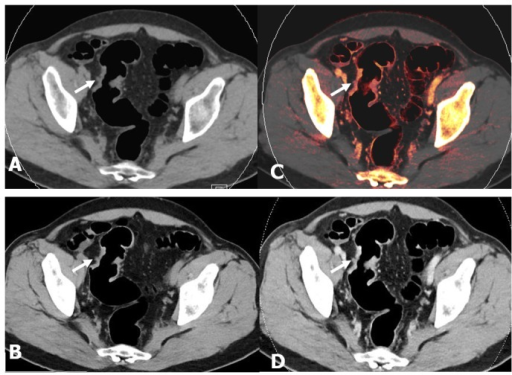

A 64 Year Old Female Patient With Sigmoid Colon Cancer Showed A Tiny Low Attenuating Lesion In The S8 Of The Liver On A Dynamic Ct Scan A C

plos.figshare.com